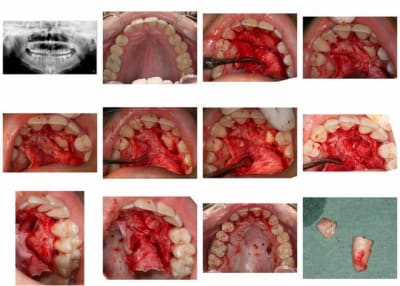

canine incluse

en dehors de ça, très belle chirurgie

> en dehors de ça, très belle chirurgie

Très joli mac et merci pour la belle iconographie!

Enfin, quel matéirel affectionnes-tu pour ce genre de chir? quelles sutures? quelles suites postop?

une lame 15, un décolleur, une fraise à os, un élevateur et du fil c'est tout.

points simples entre chaque dent.